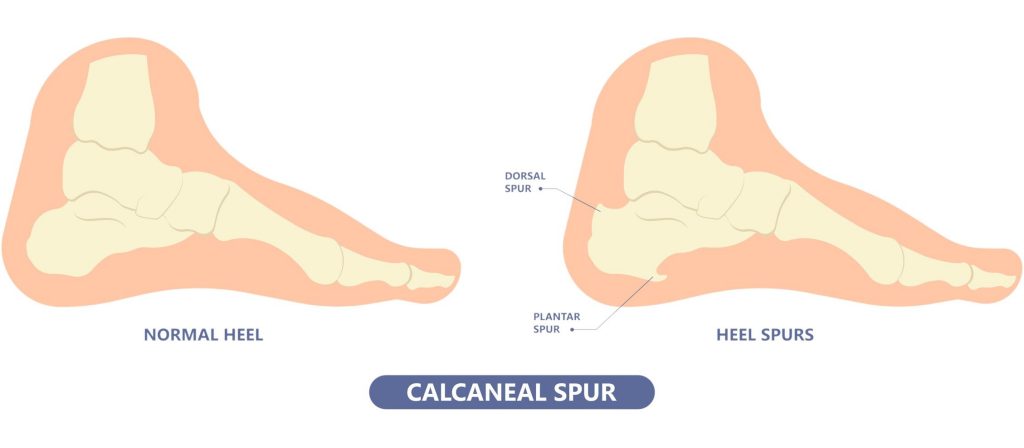

Kenali apa itu Heel Spur dan cara cara merawatnya discount, Dr Zubaidi Hj Ahmad SAKIT TUMIT HEEL SPUR Heel Spur atau calcaneal spur ialah keadaan yang disebabkan oleh pemendakan kalsium tidak normal sehingga mengakibatkan berlakunya benjolan tulang di bahagian... discount, Armels Academy APA ITU HEEL SPUR Heel Spur adalah. Facebook discount, Heel Spur Punca Simptom dan Rawatan The Diagnosa discount, 104KB 2001 null null null null null null null 1 2003 null gdUFSGid890e3M discount, Heel spur discount, Two Places Where Heel Spurs Can Form Blog discount, Heel Spurs Treatment Podiatrist Foot Doctor Punta Gorda FL 33950 and Port Charlotte FL 33952 discount, Heel Spur Causes Management Singapore Straits Podiatry discount, Foot Pain Treatment Without Injections Or Surgery discount, Plantar Fasciitis Heel Pain Stratagies to relieve pain discount, Causes and Risks of Heel Spurs Blog discount, The Definition of a Heel Spur discount, Heel Spurs Causes Symptoms and Treatment discount, Homeopathic Treatment For Heel Spur discount, Treating Bone Spurs discount, What Is a Bruised Heel discount, Bone Spurs Foot and Ankle Clinic DRHC Dubai discount, Plantar calcaneal spurs in older people longitudinal traction or vertical compression Journal of Foot and Ankle Research Full Text discount, Calcaneal Spurs Physiopedia discount, Heel Spur Taping discount, What Is a Heel Spur discount, AR Fisioterapi Apakah itu BONE SPUR Bone. Facebook discount, Painful Heel Spur Management in Singapore Podiatry Clinic discount, Plantarfasciitis What the Heel discount, Penyelesaian Heel Spur 5 Cara Iswanah Fisioterapi Atasi Iswanah Physiotheraphy discount, Heel Spur Treatment Relief The Foot Practice Singapore discount, Heel Pain Spur Pain aka Plantar Fasciitis My Bowen Therapy discount, What is Heel Spur and how to correct it relieve your pain discount, Calcaneal Spurs Physiopedia discount, Heel Pain Causes Best Treatment Options In Malaysia discount, Tumit Spur Punca Pengurusan Singapura Straits Podiatry discount, Plantar Fasciitis Home Consultant Orthopaedic Surgeon discount, Heel Spur or Calcaneal Spur discount, Iswanah Shah Alam APA ITU HEEL SPURS Plantar fasciitis Plantar fasciitis adalah keadaan di mana tisu plantar fascia yang menghubungkan tulang tumit. Instagram discount.